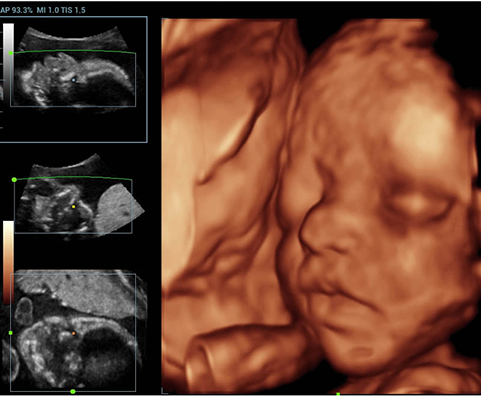

Лицо эмбриона, 3D